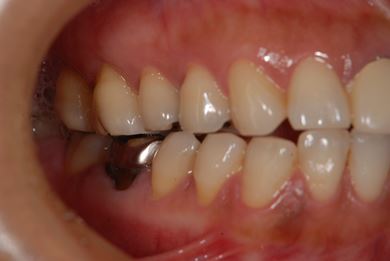

インプラントの症例写真 IMPLANT

| 主訴 | 以前治療した歯の歯ぐきから出膿。他の歯科でインプラントかブリッジしか方法がないが、骨の状態からインプラント治療は無理かもしれないと言われたことに不安を感じ、セカンドオピニオンを求めて来院。 | ||||||||||||||||||||||||||||||||

| 治療方針 | 保存不能の歯を抜歯し、インプラント治療にて機能的・審美的回復を行う。 | ||||||||||||||||||||||||||||||||

| 治療内容 | インプラント1本、ハイブリッドセラミッククラウン1本 | ||||||||||||||||||||||||||||||||